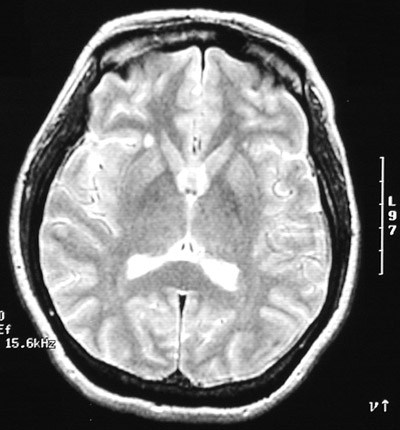

The T2 weighted MRI scan in axial view above and the axial FLAIR scan below both reveal a bright focus on the right lateral to the basal ganglia and another smaller bright focus on the left in a patient with an exacerbation of multiple sclerosis.